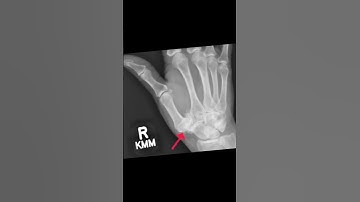

How a Tendon Can Replace an Arthritic Thumb Joint: Thumb Base Arthroplasty